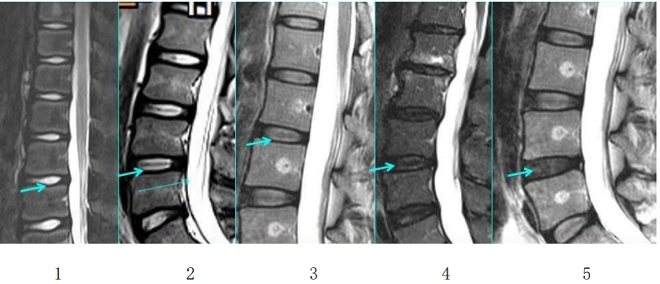

来!带你快速了解腰椎间盘突出症

来!带你快速了解腰椎间盘突出症来!带你快速了解腰椎间盘突出症01什么是腰椎间盘突出症(简称腰脱症)?腰椎间盘就像轮胎,外面一层是韧性较强的外胎,里面包裹着韧性较弱的内胎,均具有一定的弹性,可以缓冲吸收相邻椎体之间的压力。正常情况下,椎…查看详情+

腰椎间盘突出症诊疗方案

腰椎间盘突出症诊疗方案腰椎间盘突出症中医治疗方案【定义】腰椎间盘突出症,又称腰椎间盘纤维环破裂症。成年人椎间盘发生退行性改变,使椎间盘失去原有的弹性,不能担负原来承担的压力。在过度劳损,体位骤变,猛力动作或暴力撞击下,纤维环…查看详情+